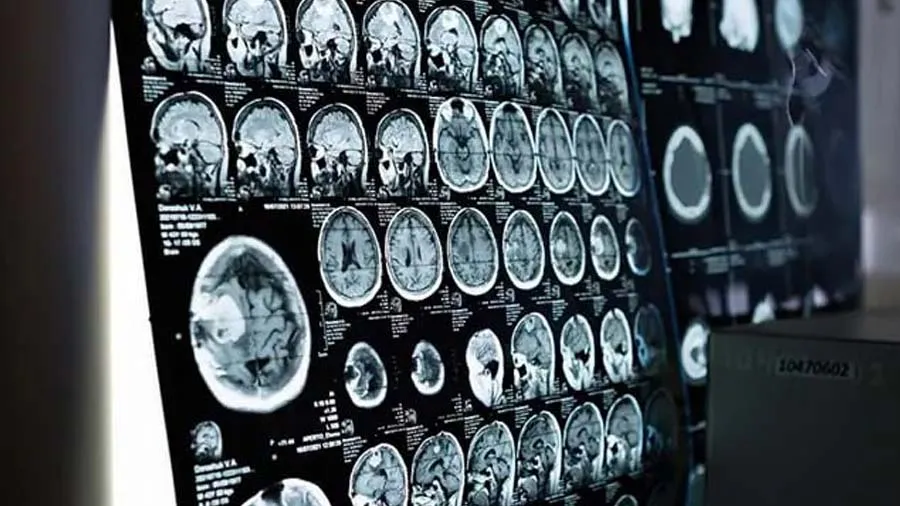

દૂષિત જળમાં જોવા મળતા એક પ્રકારની અમીબાના કારણે થનાર દુર્લભ બ્રેન ઇન્ફેક્શનથી કેરળના અલપ્પુઝા જિલ્લામાં એક કિશોરનું મોત થઈ ગયું. રાજ્યના સ્વાસ્થ્ય મંત્રી વીણા જોર્જે શુક્રવાર (7 જુલાઇના રોજ)એ આ જાણકારી આપી હતી. કેરળના અલપ્પુઝા જિલ્લાના પનાવલ્લીનો રહેવાસી 15 વર્ષીય કિશોર પ્રાઇમરી અમીબા મેનિંગોએન્સેફલાઇટિસ (PAM)થી સંક્રમિત હતો. મંત્રી વીણા જોર્જે કિશોરના મોતની પુષ્ટિ કરતા જણાવ્યું કે રાજ્યમાં પહેલા આ દુર્લભ બીમારીના 5 કેસ સામે આવી ચૂક્યા છે.

એક મીડિયા રિપોર્ટ મુજબ, અમીબા વર્ગના રોગજનક જે પરોપજીવી પ્રકૃતિના પાણી વિના સ્વતંત્ર રૂપે રહે છે, નાળા કે તળાવમાં સ્નાન કરવાથી નાકની પાતળી ત્વચાના માધ્યમથી માનવ શરીરમાં પ્રવેશે છે અને એન્સેફલાઇટિસનું કારણ બને છે જે મસ્તિષ્કને ગંભીર રૂપે પ્રભાવિત કરે છે. તેના મુખ્ય લક્ષણ, તાવ, માથાનો દુઃખાવો, ઉલ્ટી અને ખેંચ આવવા છે. પ્રાથમિક અમીબા મેનિંગોએન્સેફલાઇટિસ એક દુર્લભ મસ્તિષ્ક સંક્રમણ છે, જે નેગાલેરિયા ફાઉલેરીનું કારણ હાય છે. તે એક અમીબા છે (એકકોષિય જીવ જે સૂક્ષ્મદર્શી ન જોઈ શકાય તેવો નાનો).